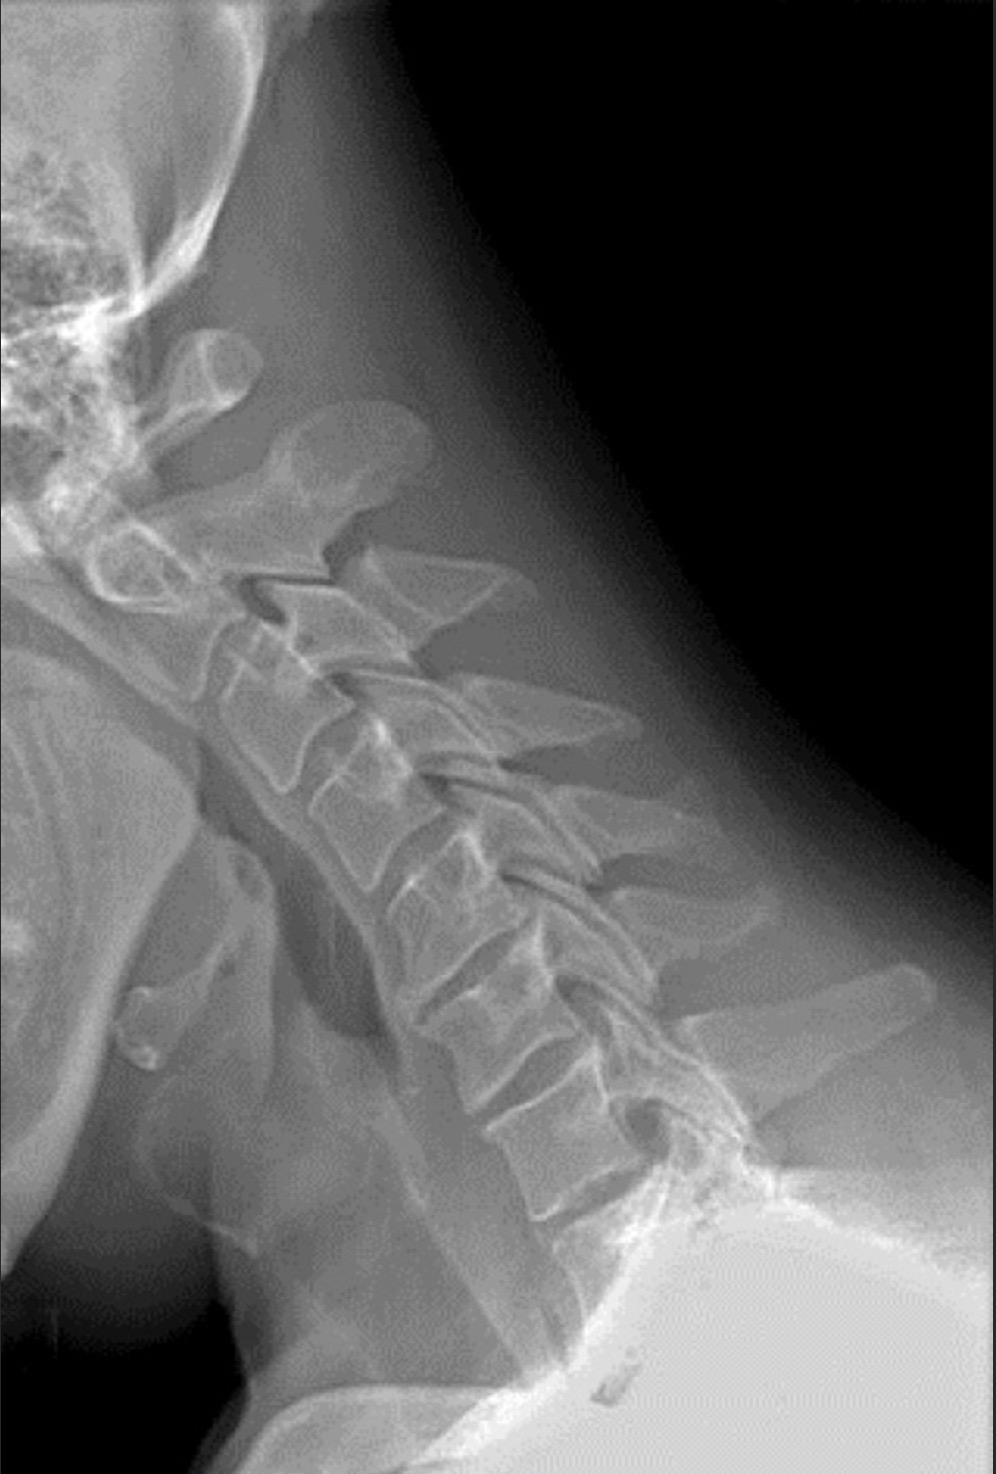

运动损伤之颈椎关节炎

颈椎关节炎是指颈椎椎体和椎间盘(位于骨头之间的圆盘,起到“避震器”作用)的退行性病变。这种退行性病变可能对颈椎产生数种影响,包括骨刺、椎间关节破裂或融合(连接一节脊柱的关节与下一节脊柱相连)、骨孔缩小(骨头上的小孔,神经从中通过)、神经根受压和颈椎管狭窄症。颈椎关节炎的典型症状包括界限模糊的或泛泛的.....

运动损伤之颈椎骨折

发生颈椎骨折的运动员通常出现各种症状,具体取决于骨折的类型及其严重程度。可能出现的症状包括颈部疼痛;脖子活动时出现疼痛;无法活动脖子;上肢麻木、刺痛或无力;或者无法移动四肢。由于颈部骨折的复杂性和潜在严重性,颈部出现疼痛的任何运动员,尤其是有过外伤史的运动员,应该由专业的医务人员进行伤情评估。.....